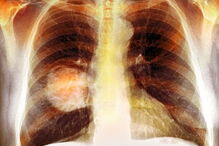

Os vírus respiratórios, como o da gripe ou SARS-CoV-2, podem ativar células cancerígenas da mama adormecidas que se espalharam para os pulmões, segundo um estudo em ratos, sobre a relação entre doenças infecciosas e metástases.

Os detalhes foram publicados na revista científica Nature, num artigo liderado por cientistas dos Estados Unidos da América (EUA), do Reino Unido e dos Países Baixos, que também recolheram dados em humanos para corroborar as conclusões.

"As nossas descobertas indicam que as pessoas com um historial de cancro podem precaver-se contra os vírus respiratórios, como vacinar-se sempre que possível", salientou codiretor do estudo Julio Aguirre-Ghiso.